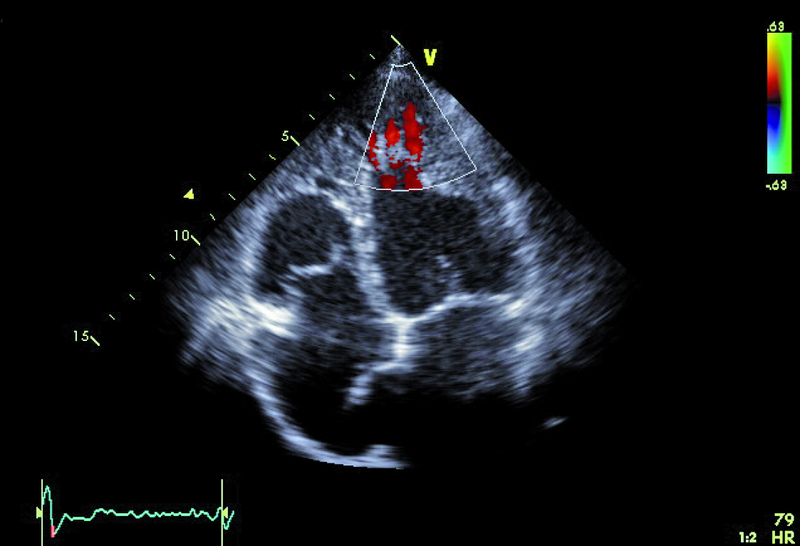

Kobieta, lat 36. Jakie patologie można rozpoznać na zamieszczonych rycinach?

5. Tętniak przegrody międzyprzedsionkowej (ryc. 4-6).

6. Ubytek przegrody międzyprzedsionkowej z przeciekiem lewo-prawym (ryc. 6).